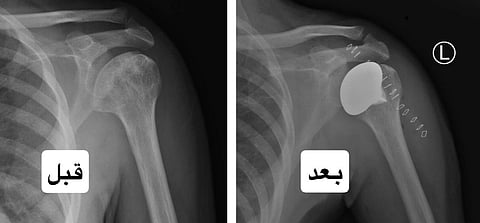

نجح فريق طبي متخصص في مدينة الملك سعود الطبية – عضو تجمع الرياض الصحي الأول – في تحقيق إنجاز طبي نوعي، تمثّل في إجراء أول عملية من نوعها لتبديل رأس عظمة العضد في مفصل الكتف، وذلك لمريض في العقد الرابع من عمره كان يعاني من مضاعفات فقر الدم المنجلي، تسببت في تنخّر لاوعائي في رأس عظمة العضد، مما أدى إلى آلام مزمنة أثرت بشكل كبير على حركة المفصل والقدرة على أداء الأنشطة اليومية.

وأوضح الدكتور بندر السهلي، استشاري جراحة العظام والأطراف العلوية وقائد الفريق الطبي، أن المريض خضع لفحوصات دقيقة شملت: الأشعة السينية والمقطعية والرنين المغناطيسي قبل اتخاذ قرار التدخل الجراحي.

وقد أُجريت العملية بنجاح - ولله الحمد - وتلقى المريض بعد العملية رعاية تأهيلية مكثفة من قِبل فريق العلاج الطبيعي والوظيفي، تمثلت في وضع خطة علاجية مناسبة لحالته.